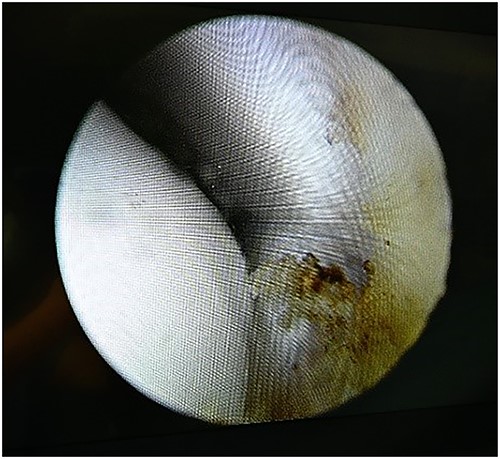

The patient underwent ankle arthroscopy (Fig. 4), mini open debridement of the affected area (Figs 5 and 6), followed by intra-articular injection of BMC derived from his own bone marrow. (Figs 7 and 8).